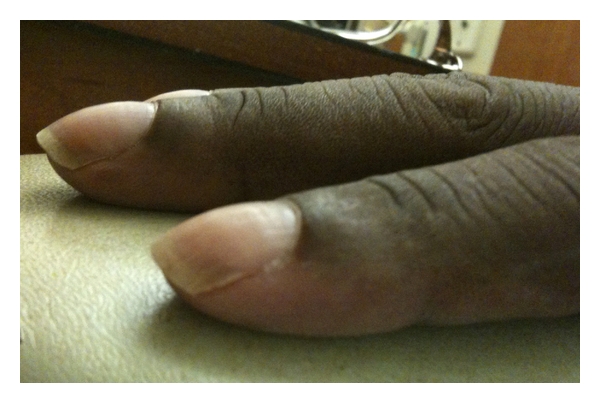

- White nails (leukonychia)

- Digital clubbing

- Acrocyanosis

- Skin changes (hyperpigmentation, hypertrichosis, glomeruloid hemangiomas, white nails)

- Fingernail clubbing